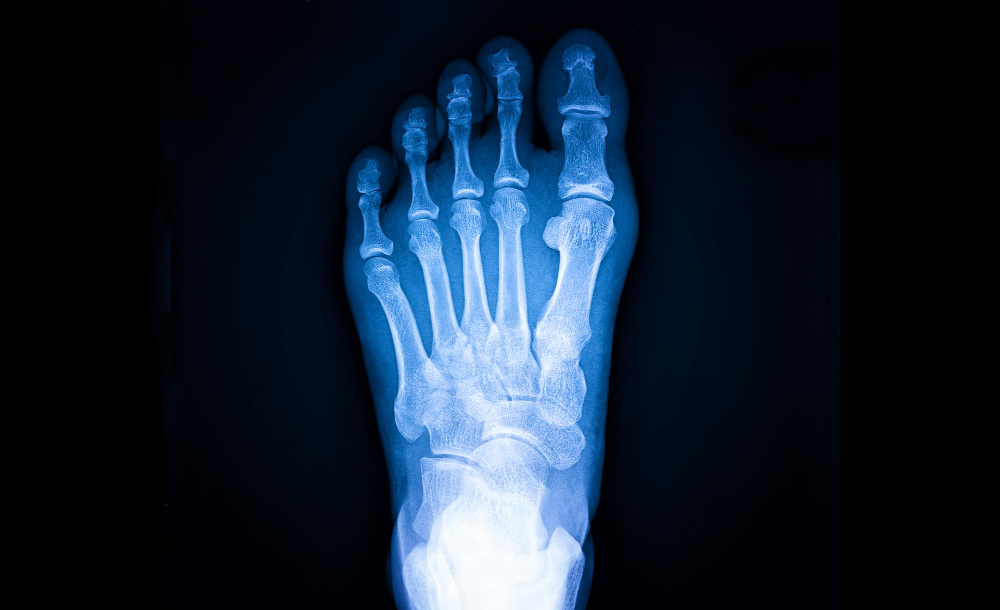

El Neuroma de Morton es una condición dolorosa que afecta los nervios entre los dedos del pie, causando dolor, ardor y entumecimiento. El Dr. Francisco Castillo Vazquez ofrece un enfoque integral para el tratamiento del Neuroma de Morton, que incluye terapias físicas, medicamentos, uso de ortesis y, en casos severos, procedimientos quirúrgicos. Su objetivo es aliviar el dolor, reducir la inflamación y mejorar la función del pie.

El tratamiento del Neuroma de Morton incluye una combinación de terapias físicas, medicamentos, uso de ortesis y, en casos severos, procedimientos quirúrgicos. El Dr. Francisco Castillo Vazquez evalúa cada caso individualmente para desarrollar un plan de tratamiento personalizado.